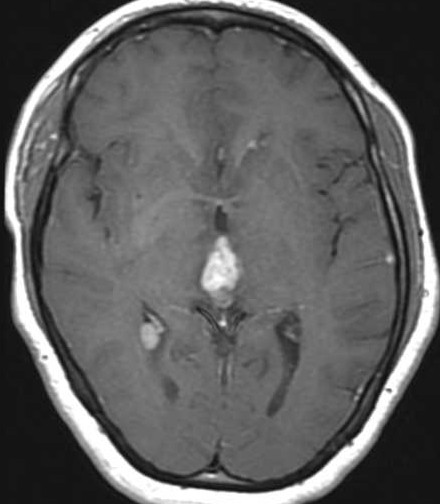

| Fem. 17a. |

| Nódulo sólido homogêneo preenchendo o III ventrículo, com limites precisos, com hipossinal em T1 e hipersinal em T2 e FLAIR, que se impregna por contraste paramagnético. Lesão menor implantada no assoalho do IV ventrículo provavelmente representa disseminação por via liquórica. |

| CORTES AXIAIS, T1 COM CONTRASTE | ||

| F. 17a. Tumor teratóide rabdóide atípico de III ventrículo. RM | HE | VIM, GFAP | HHF35, desmina, 1A4 | AE1AE3, EMA |